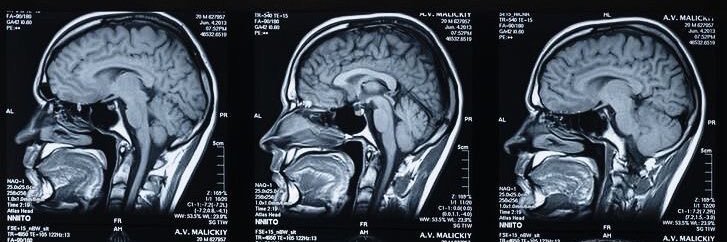

Diagnostic radiology resident |Highlights 4 medical students |ملك الشاهي